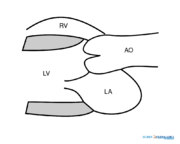

| 08:40, 15 May 2008 | PLAX.svg (file) |  |

38 KB | April | 1 | |